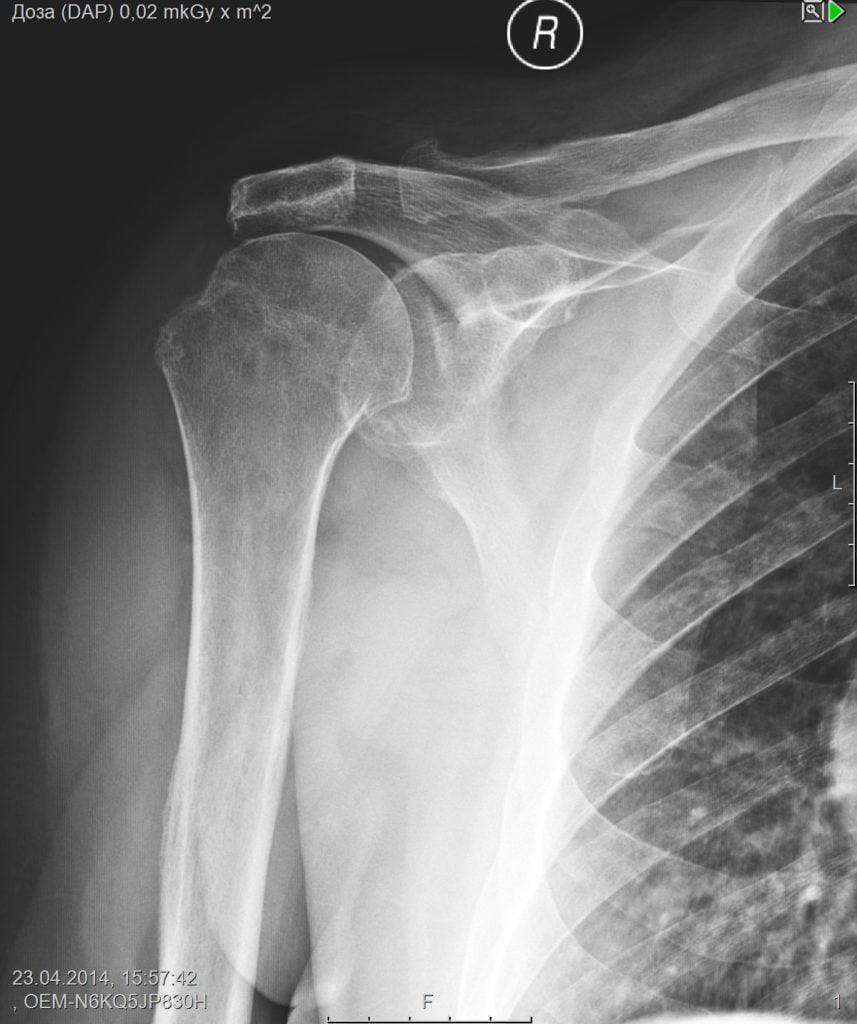

- рентгенографию плеча – опытный врач сможет заметить уменьшение расстояния между дистальным концом лопатки и ключицей;

Все вопросы снимает только магнитно-резонансное обследование. Четко видно разрушение суставной капсулы, уменьшение количества хрящевой ткани в полости сочленения, краевые костные разрастания.